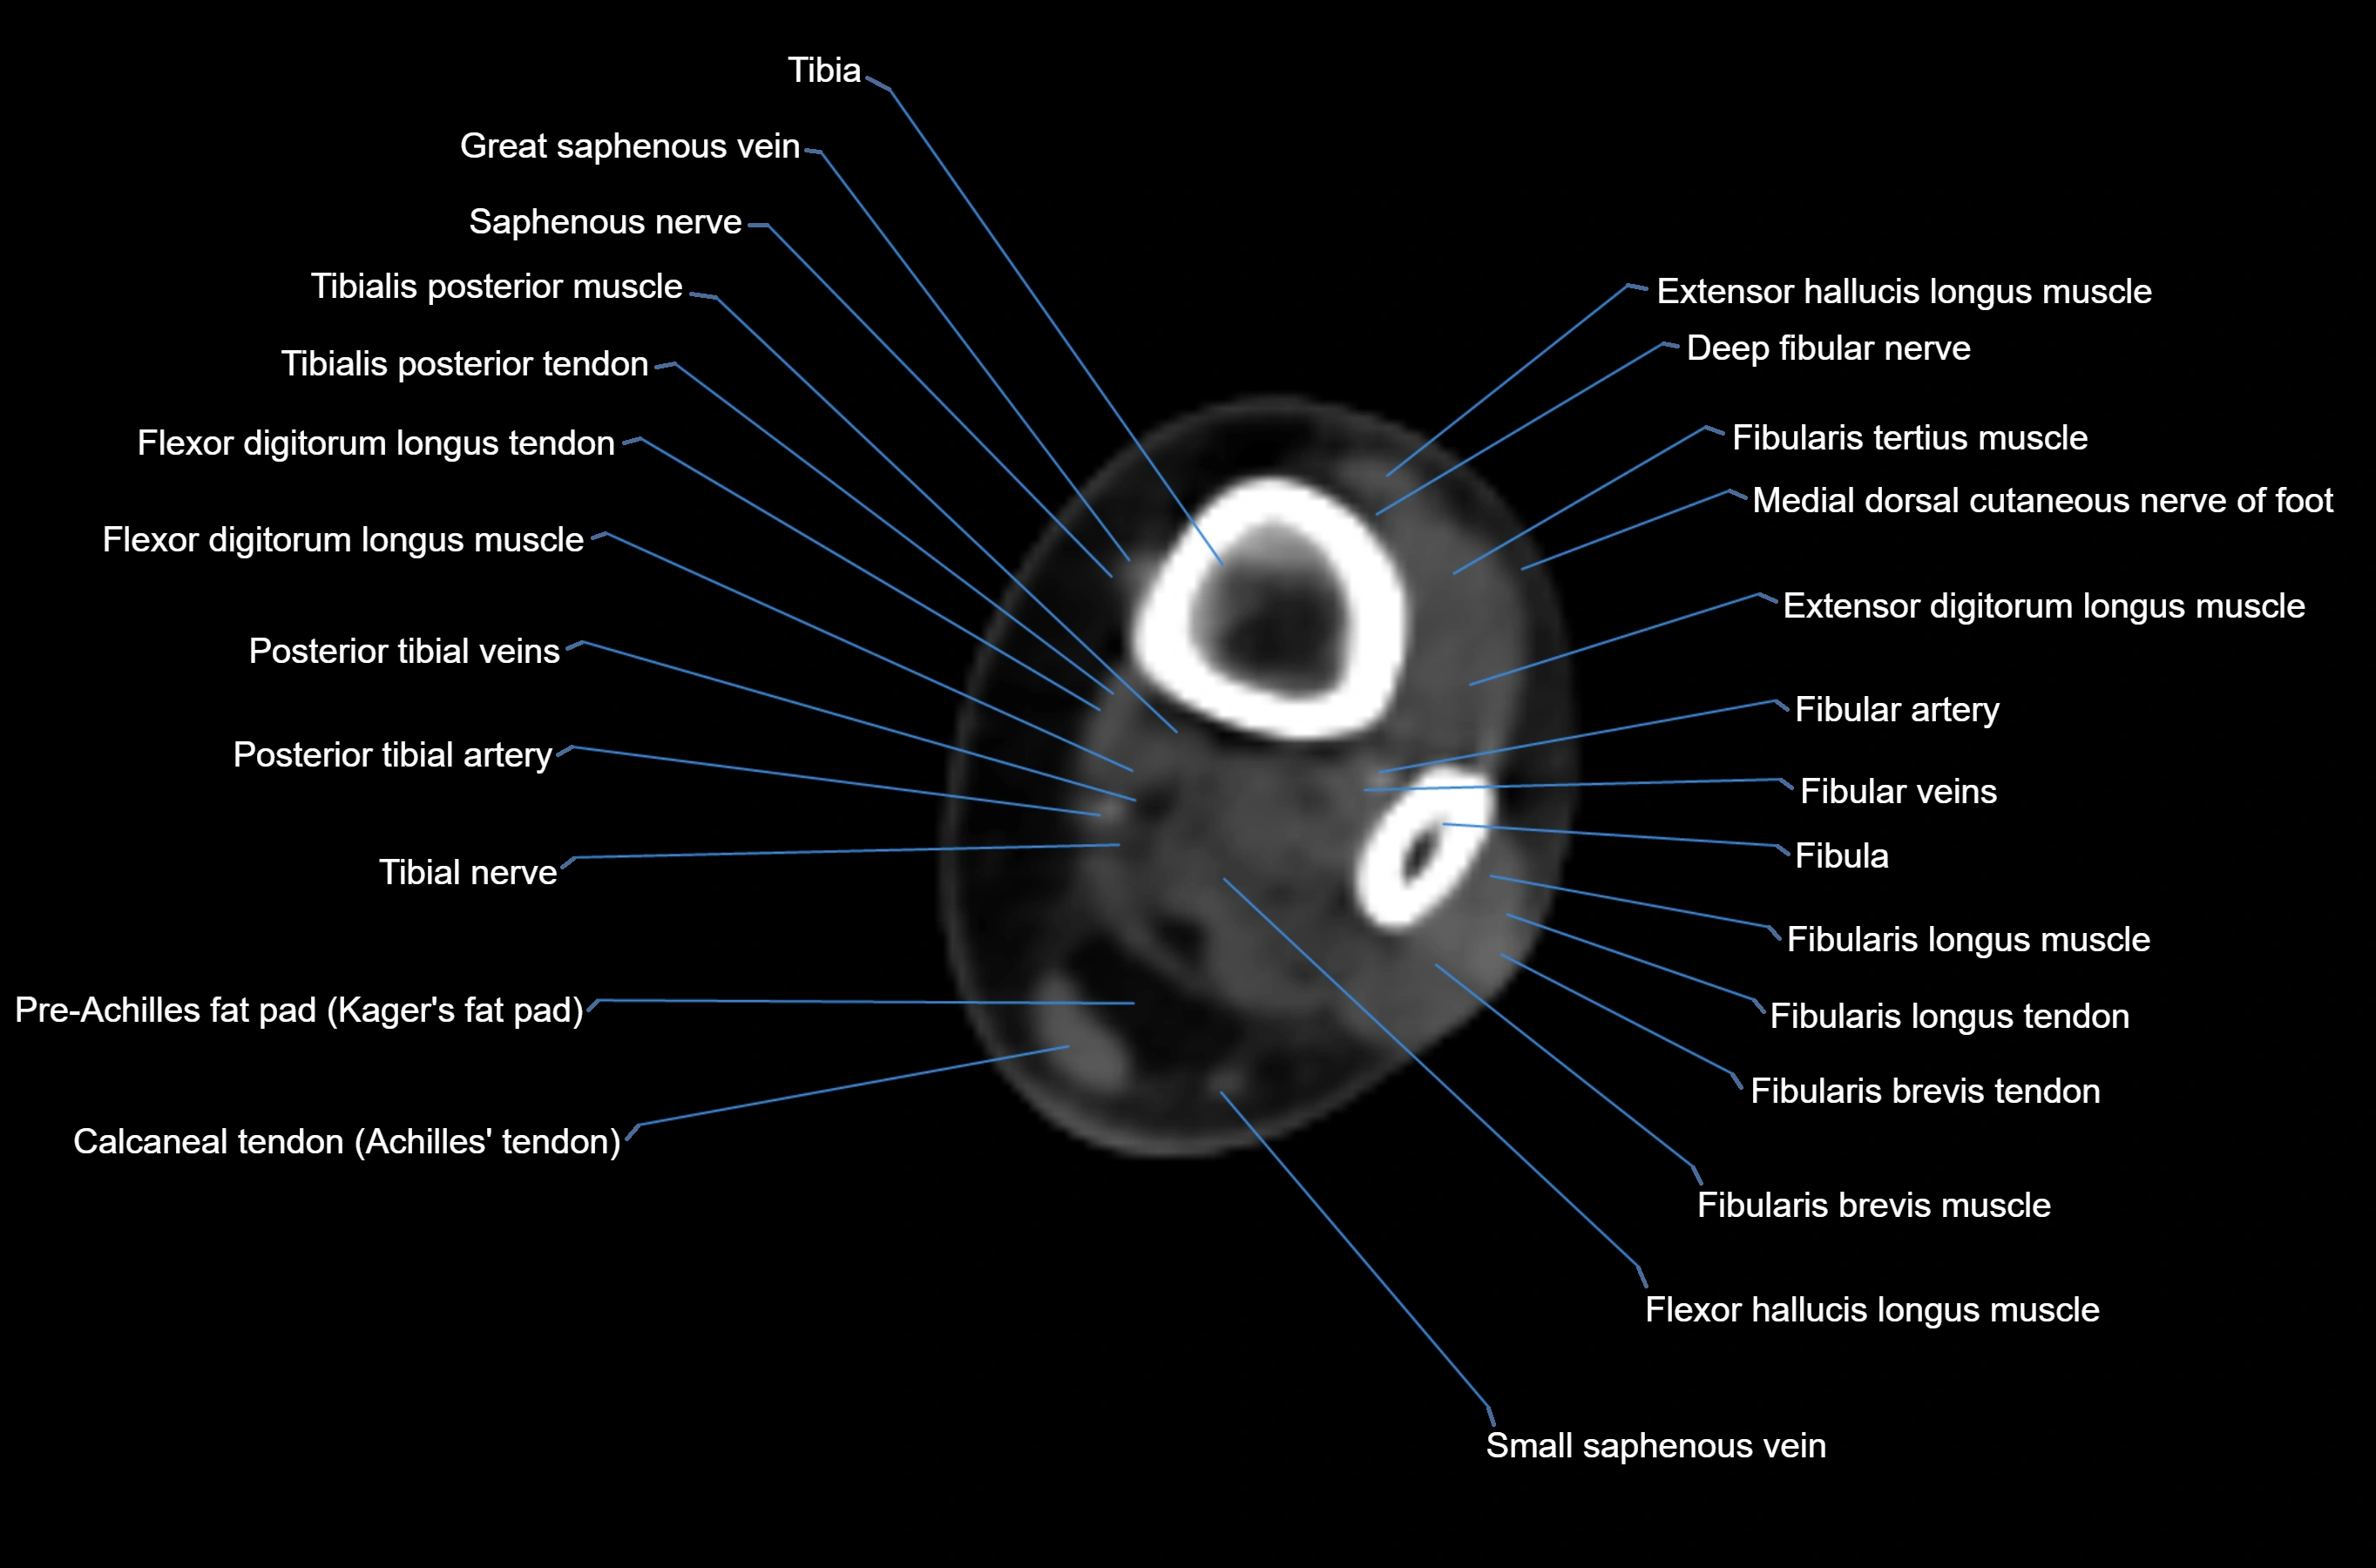

- Fibula

- Fibular artery

- Fibular veins

- Fibularis brevis muscle

- Fibularis brevis tendon

- Fibularis longus muscle (peroneus longus muscle)

- Fibularis longus tendon

- Fibularis tertius muscle

- Flexor digitorum longus muscle

- Flexor digitorum longus tendon

- Flexor hallucis longus muscle

- Flexor hallucis longus tendon

- Gastrocnemius muscle

- Kager fat pad (pre-Achilles fat pad)

- Posterior tibial artery

- Posterior tibial veins

- Saphenous nerve

- Small saphenous vein

- Tibia

- Tibial nerve

- Tibialis posterior muscle

- Tibialis posterior tendon